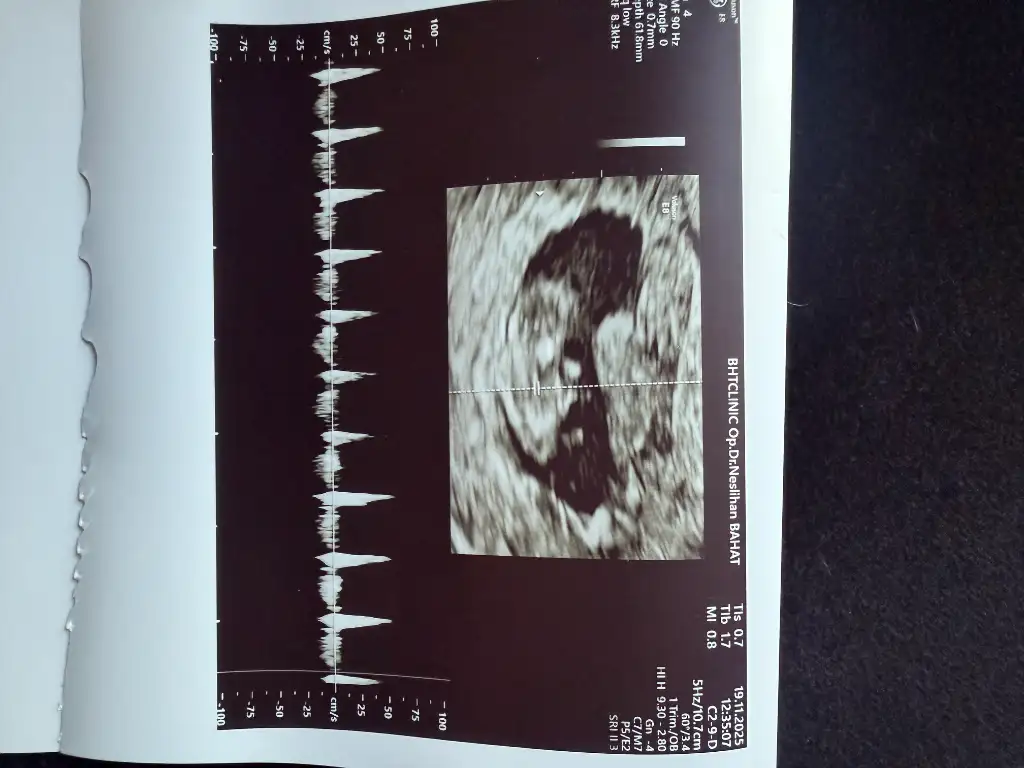

Kızlar doktordan gelıyorum 10hafta bıttı cok sukur kanama alanı hala mevcut 2hafta sonra ense kalınlıgı ıcın cagırdı sızce cınsıyet ne olabılır

Eklentiler

• IMG_4811.webp

IMG_4811.webp

35,9 KB · Görüntüleme: 28